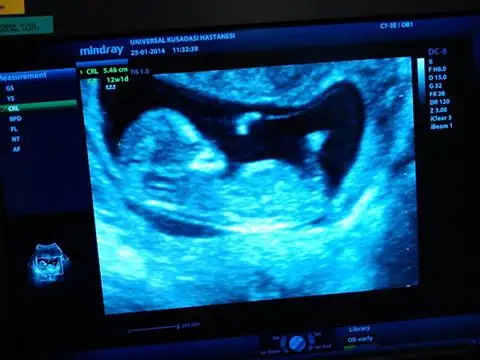

kızlar tecrübeli arkadaşlardan yorum rica ediyorum. doktorum%85-90 erkek dedi. henüz 12. haftamdayım. $2014-02-12 18.18.41.webp

şimdiden teşekkür ederim..

kızlar tecrübeli arkadaşlardan yorum rica ediyorum. doktorum%85-90 erkek dedi. henüz 12. haftamdayım. Eki Görüntüle 977889